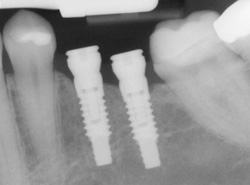

If you've lost a tooth, dental implants can rejuvenate both your smile and your oral health. An implant is a synthetic tooth root in the shape of a post that is surgically placed into the jawbone. The “root” is usually made of titanium — the same material used in many replacement hips and knees, and a metal that is well suited to pairing with human bone. A replacement tooth is fixed to the post. The tooth can be either permanently attached or removable. Permanent teeth are more stable and feel more like natural teeth.

Implants are versatile. If you are only missing one tooth, one implant plus one replacement tooth will do the trick. If you are missing several teeth in a row, a few strategically placed implants can support a permanent bridge (a set of replacement teeth). Similarly, if you have lost all your teeth, a full bridge or full denture can be permanently fixed in your mouth with a strategic number of implants.